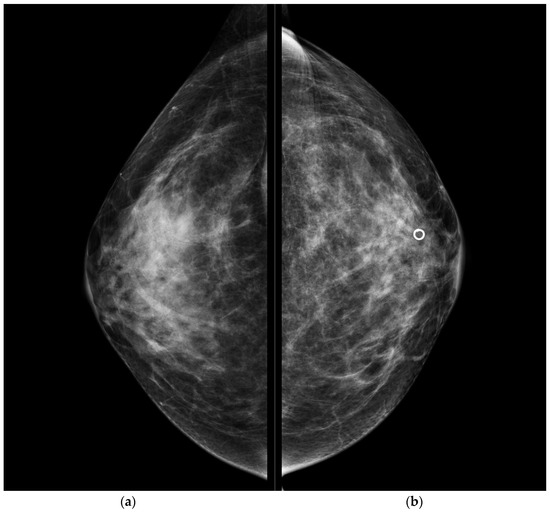

CESM also confirmed the presence of a metallic marker in the left retro-areolar breast, previously released in the breast biopsy site (Figure 1, Figure 2, Figure 3 and Figure 4).

Figure 1. Conventional CC projections of the right breast (a) and left breast (b). A circular-shape marker released after US-guided biopsy was seen in the retro-areolar left breast. No suspicious mammographic findings were detected.